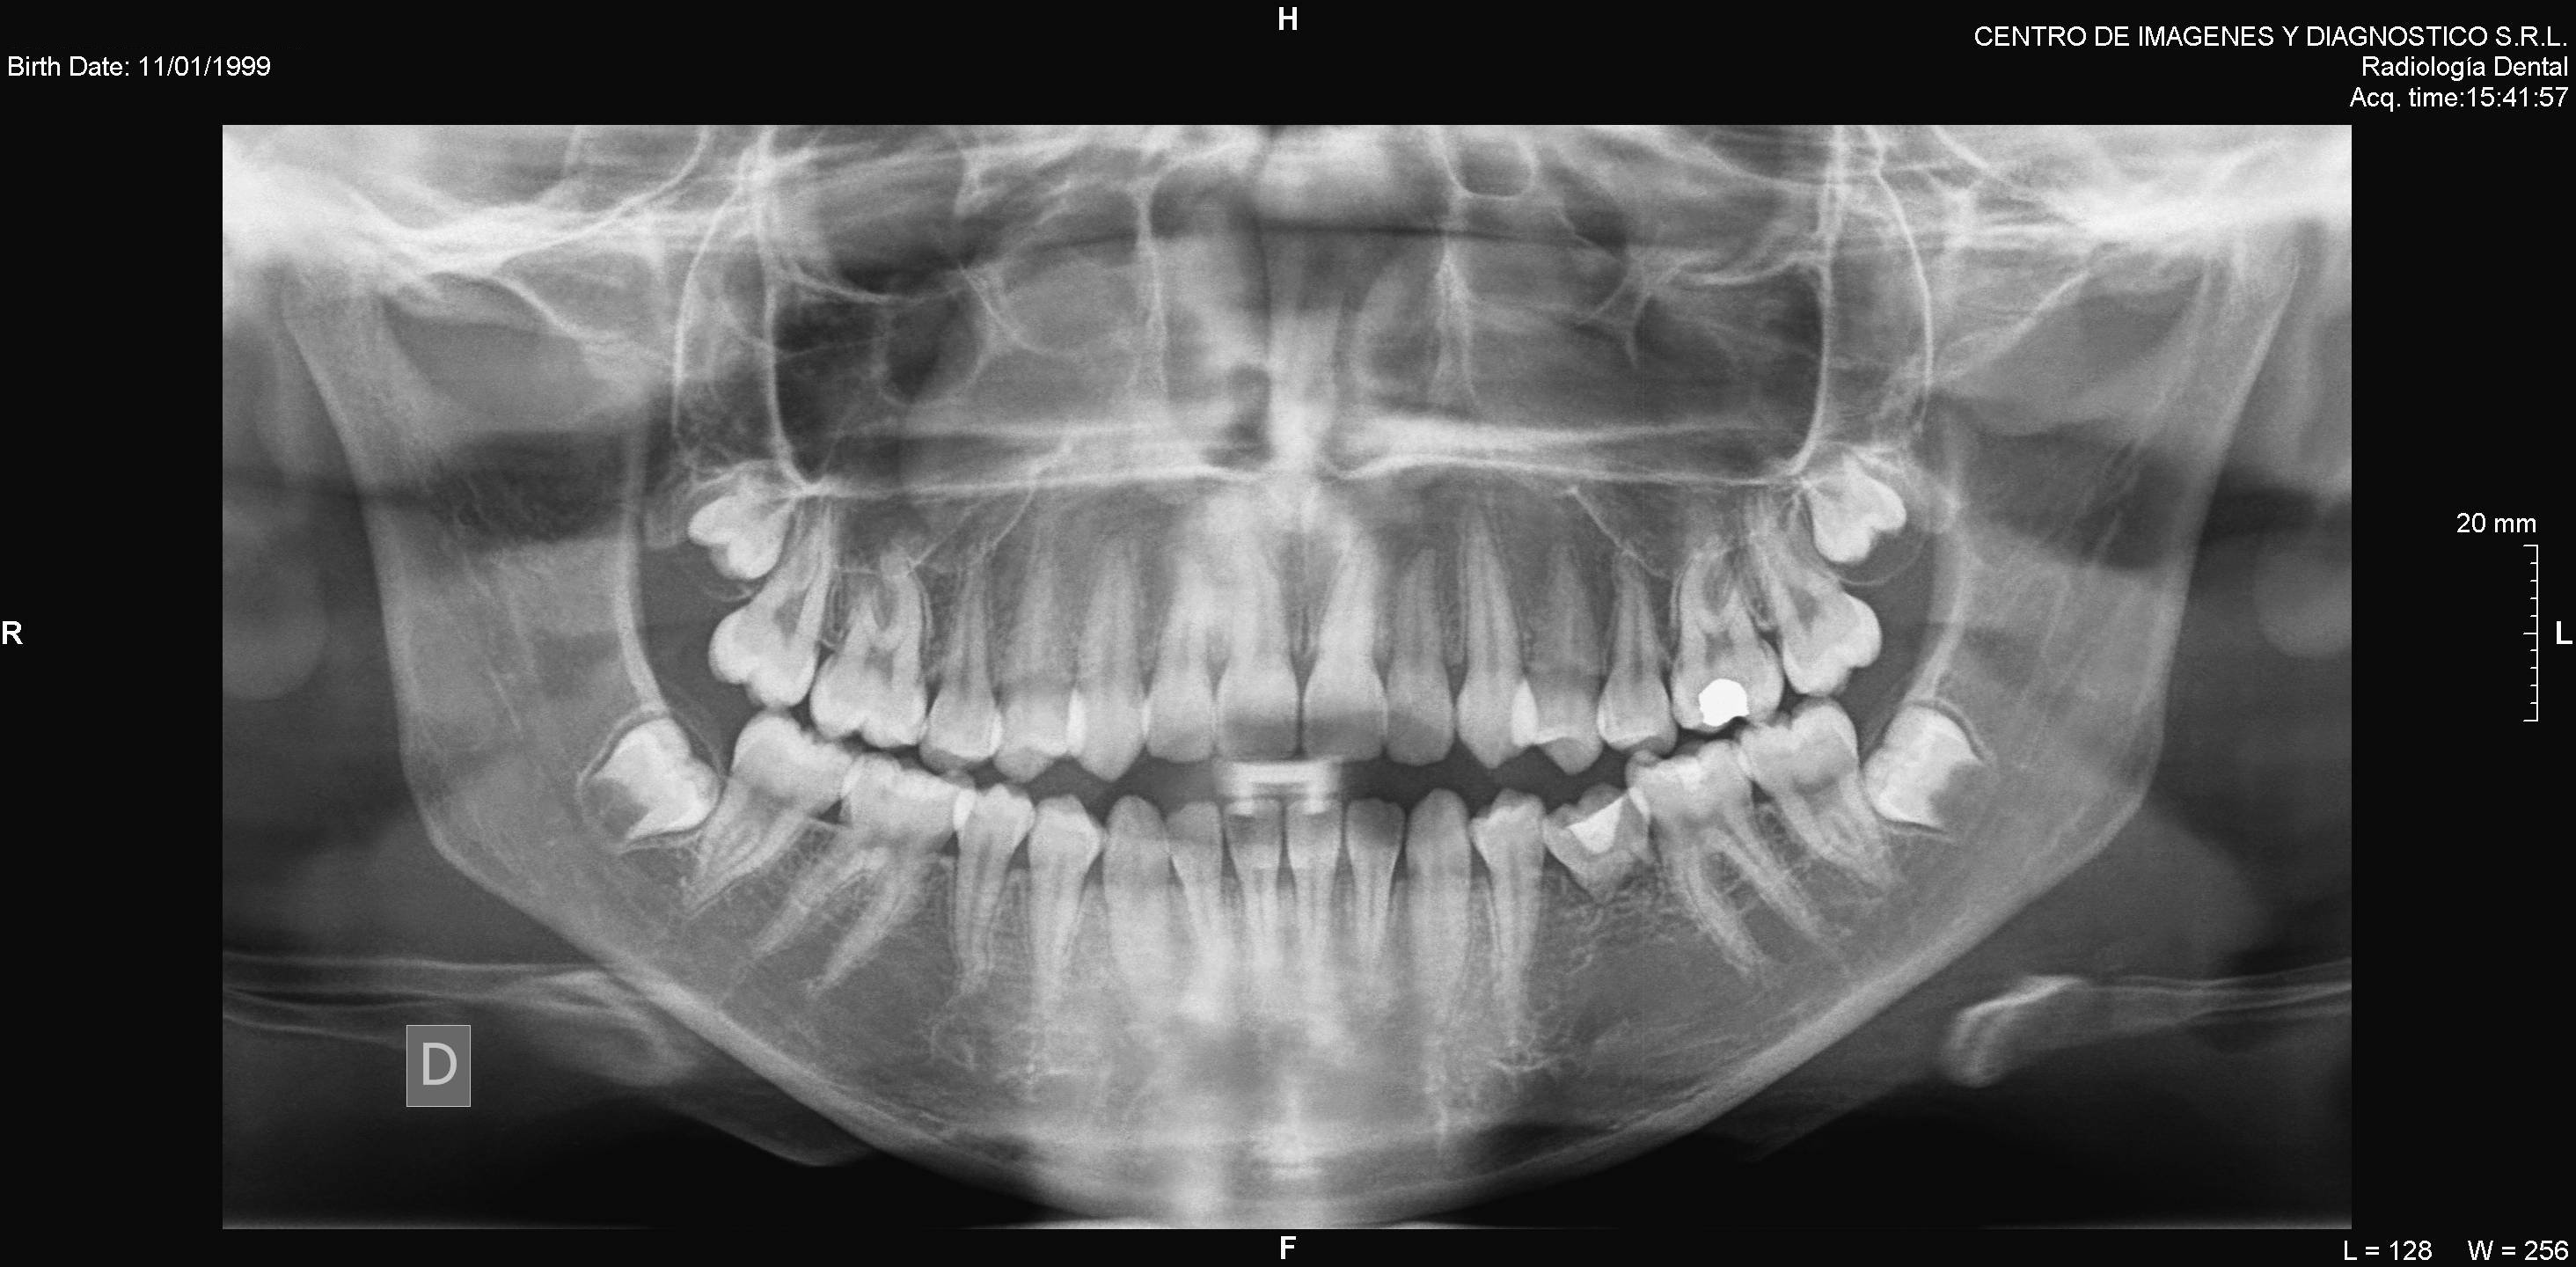

Algunos ejemplos de imágenes digitales

Pulse en las imágenes para ver la ampliación

14lado